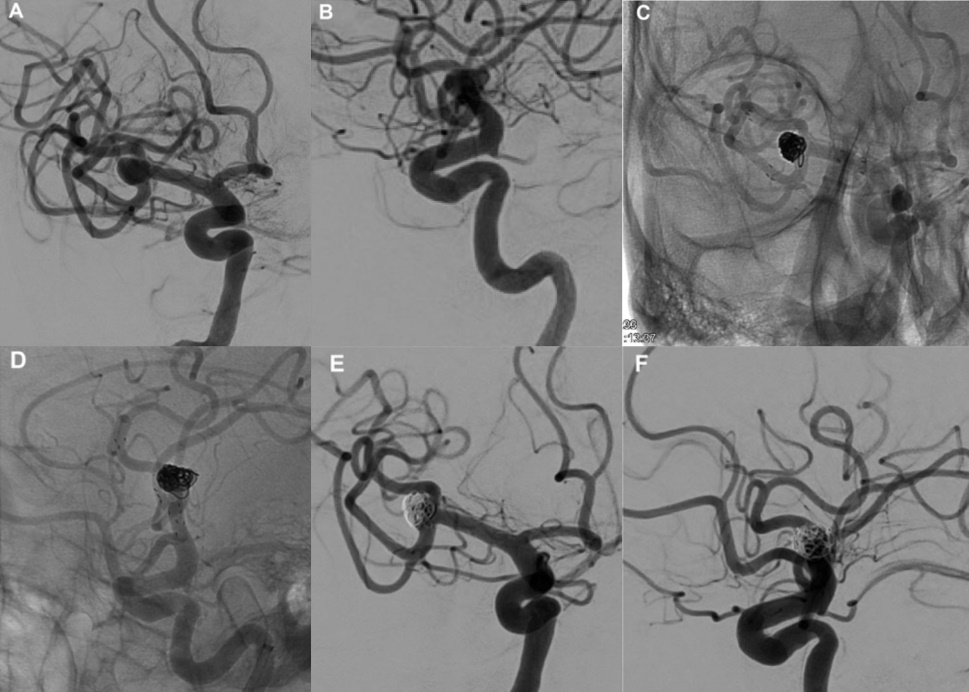

我院首例neuroform atlas支架应用于破裂的大脑中动脉宽颈动脉瘤.

neuroformatlas支架在实现y型支架治疗颅内宽颈分叉动脉瘤中的应用

基底尖动脉瘤y型开环支架辅助栓塞

neuroformatlas支架治疗颅内动脉瘤